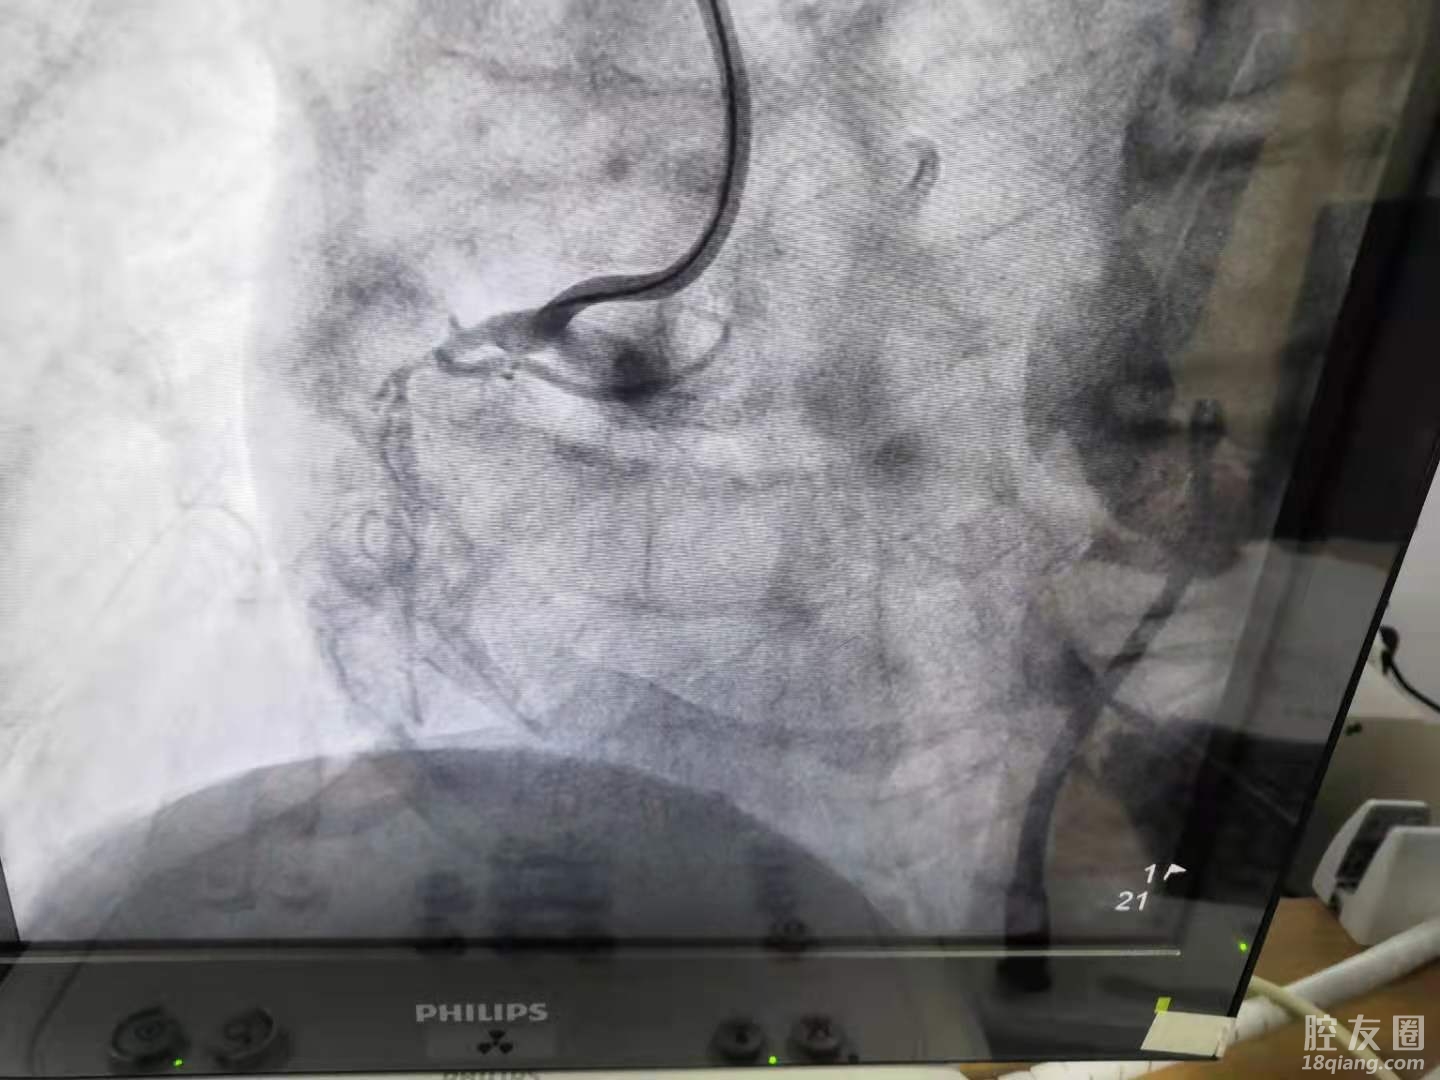

(术后)

术中,李主任对于闭塞的右冠状动脉,选择经右桡动脉,通过超强支撑导引导管7F AL1,左冠状动脉经股动脉也使用导引导管,对侧造影指引,反复尝试后,在微导管支撑下,第三根导丝成功通过病变。

一般情况下,导丝通过病变,手术很快就会结束,但该患者不一样,对于整场手术的艰苦战斗刚刚开始,因张先生右冠状动脉严重钙化,就像石头一样,器械难以通过,甚至造成微导管头端毁损,及球囊受损,难度很大。术中,李主任利用各种手术技巧,克服困难,前后一共使用了9个球囊,历经两个半小时,终于将病变顺利扩张,并在延长导管支持下,为患者成功植入两枚支架,顺利开通血管,完成手术。目前患者恢复良好,已顺利康复出院,后期定期复查即可。